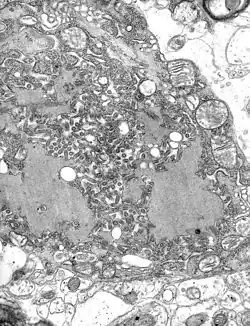

TEM micrograph with numerous rabies virions (small, dark grey, rodlike particles) and Negri bodies (the larger pathognomonic cellular inclusions of rabies infection)

The rabies virus is the type species of the Lyssavirus genus, in the family Rhabdoviridae, order Mononegavirales. Lyssavirions have helical symmetry, with a length of about 180 nm and a cross-section of about 75 nm.[34] These virions are enveloped and have a single-stranded RNA genome with negative sense. The genetic information is packed as a ribonucleoprotein complex in which RNA is tightly bound by the viral nucleoprotein. The RNA genome of the virus encodes five genes whose order is highly conserved: nucleoprotein (N), phosphoprotein (P), matrix protein (M), glycoprotein (G), and the viral RNA polymerase (L).[35]

Rabies can be difficult to diagnose because, in the early stages, it is easily confused with other diseases or even with a simple aggressive temperament.[63] The reference method for diagnosing rabies is the fluorescent antibody test (FAT), an immunohistochemistry procedure, which is recommended by the World Health Organization (WHO).[64] The FAT relies on the ability of a detector molecule (usually fluorescein isothiocyanate) coupled with a rabies-specific antibody, forming a conjugate, to bind to and allow the visualisation of rabies antigen using fluorescent microscopy techniques. Microscopic analysis of samples is the only direct method that allows for the identification of rabies virus-specific antigen in a short time and at a reduced cost, irrespective of geographical origin and status of the host. It has to be regarded as the first step in diagnostic procedures for all laboratories. Autolysed samples can, however, reduce the sensitivity and specificity of the FAT.[65] The RT PCR assays proved to be a sensitive and specific tool for routine diagnostic purposes,[66] particularly in decomposed samples[67] or archival specimens.[68] The diagnosis can be reliably made from brain samples taken after death. The diagnosis can also be made from saliva, urine, and cerebrospinal fluid samples, but this is not as sensitive or reliable as brain samples.[65] Cerebral inclusion bodies called Negri bodies are 100% diagnostic for rabies infection but are found in only about 80% of cases.[34] If possible, the animal from which the bite was received should also be examined for rabies.[69]